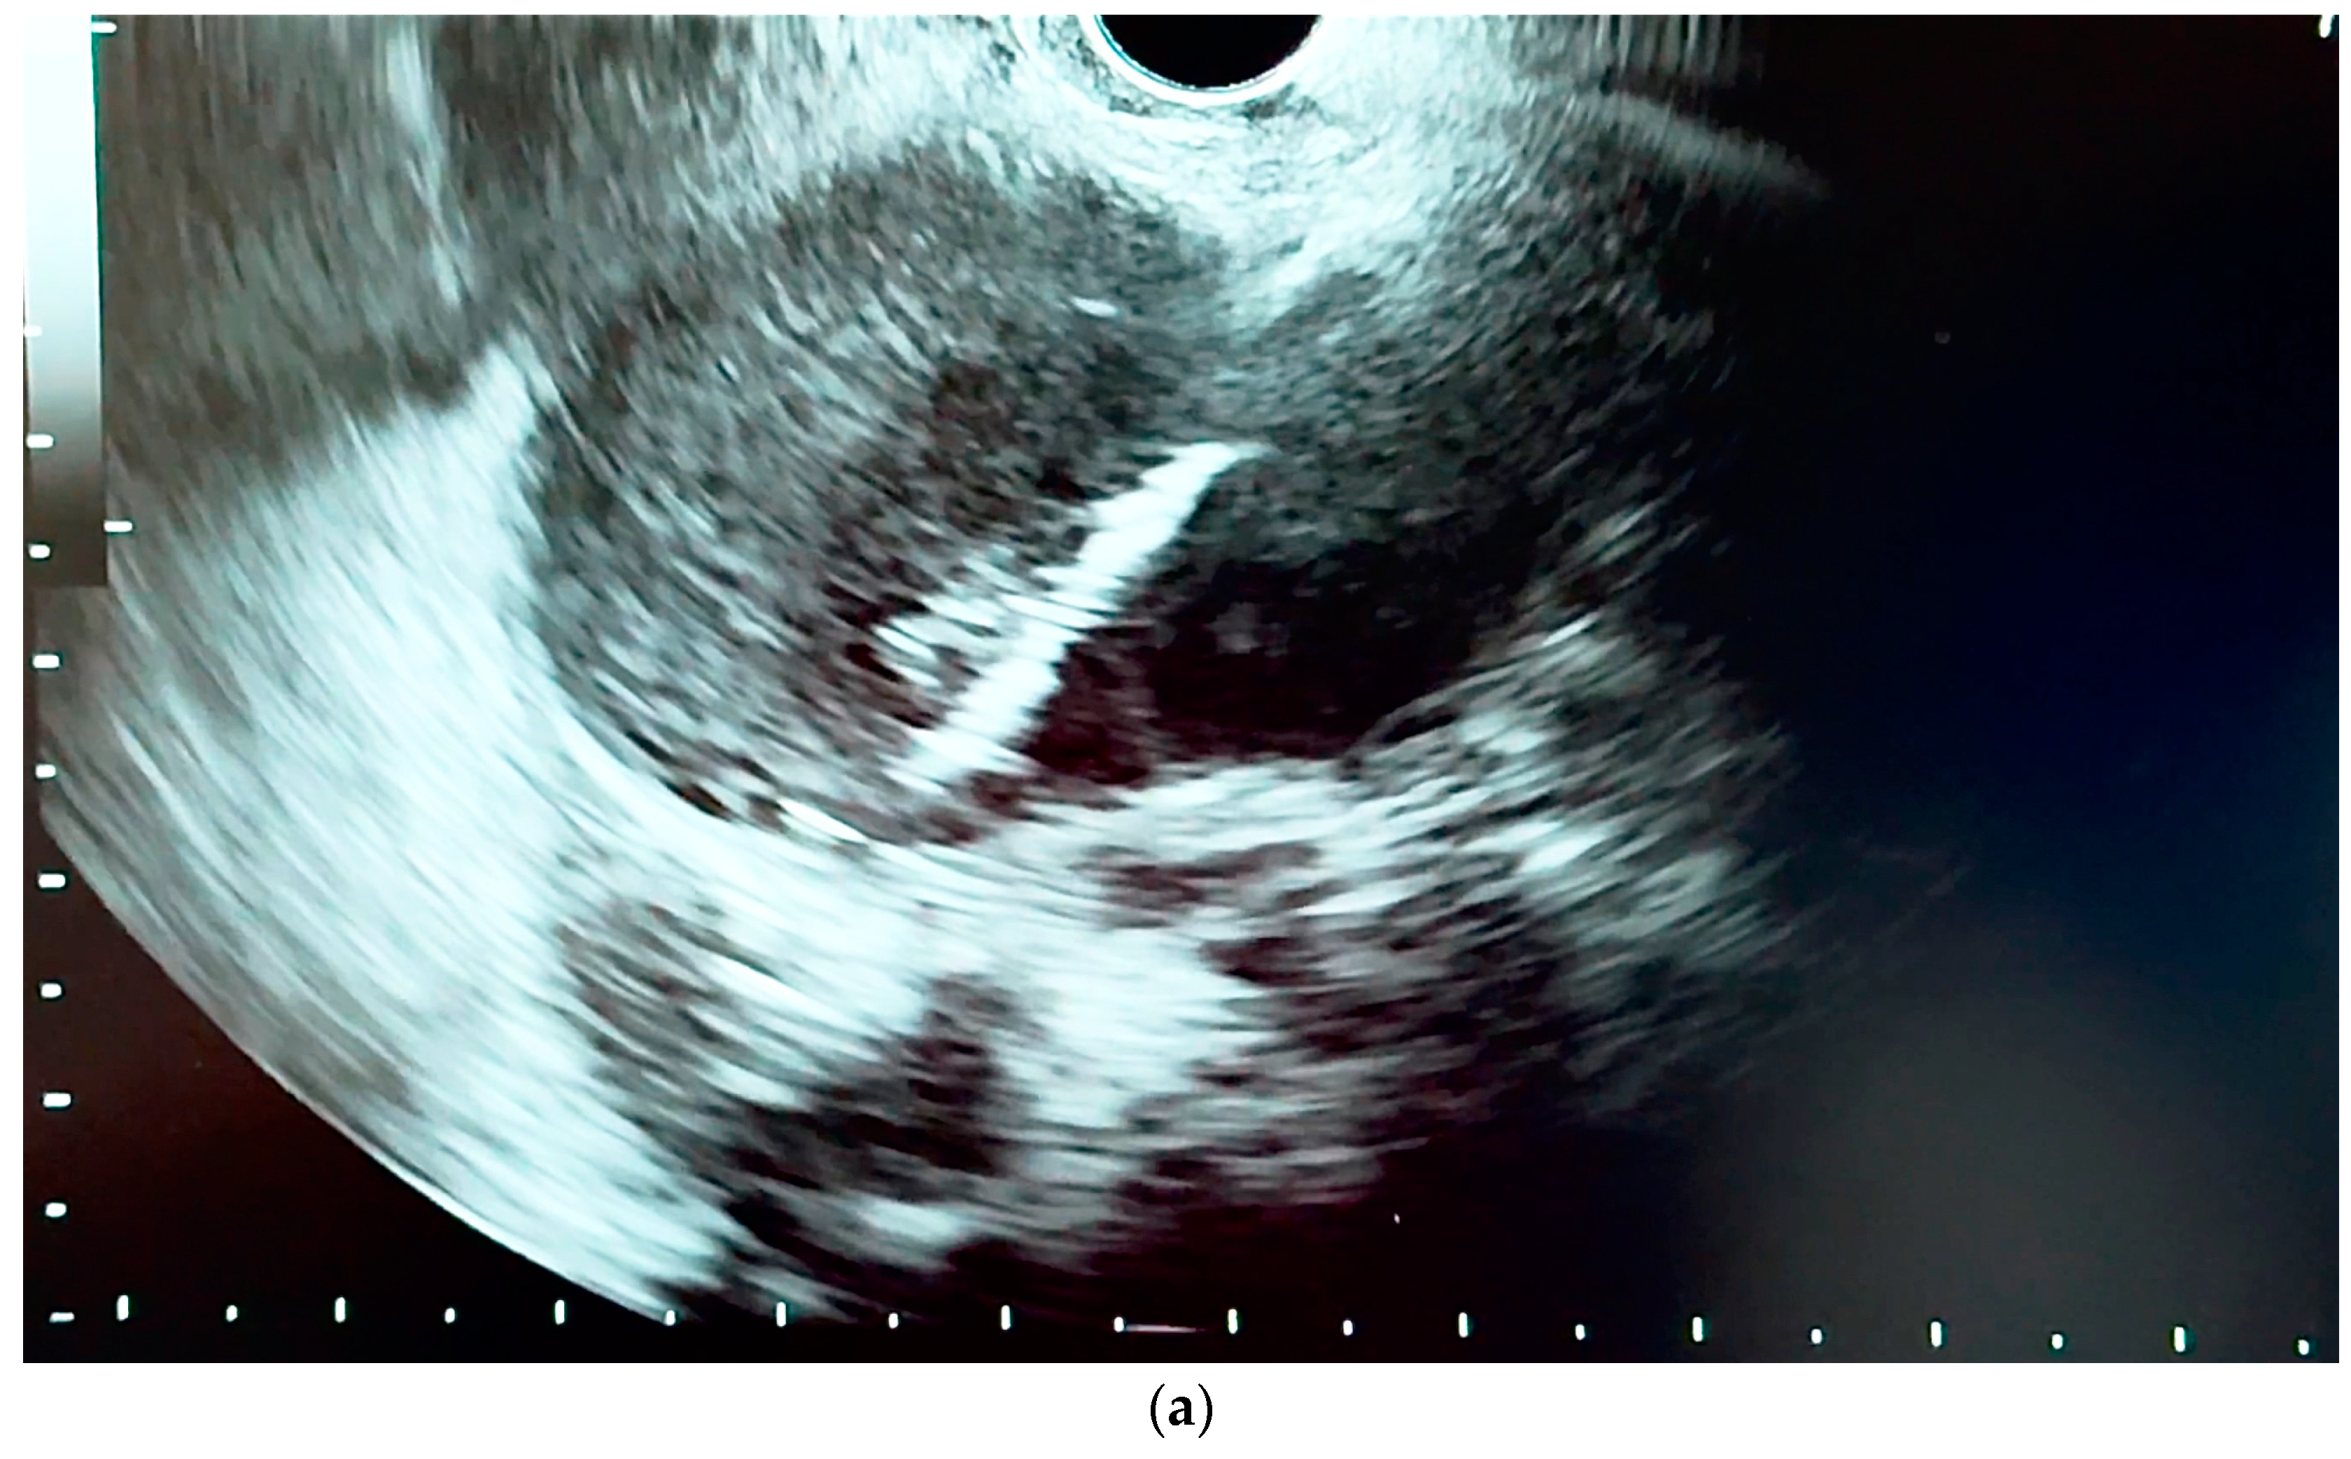

6.4.1. Endoscopic Ultrasound (EUS)

- Orzan, R.I.; Pojoga, C.; Agoston, R.; Seicean, R.; Seicean, A. Endoscopic Ultrasound in the Diagnosis of Extrahepatic Cholangiocarcinoma: What Do We Know in 2023? Diagnostics 2023, 13, 1023. [Google Scholar] [CrossRef] [PubMed]

- Otsuka, Y.; Kamata, K.; Hyodo, T.; Chikugo, T.; Hara, A.; Tanaka, H.; Yoshikawa, T.; Ishikawa, R.; Okamoto, A.; Yamazaki, T.; et al. Utility of contrast-enhanced harmonic endoscopic ultrasonography for T-staging of patients with extrahepatic bile duct cancer. Surg. Endosc. 2022, 36, 3254–3260. [Google Scholar] [CrossRef] [PubMed]

- Strongin, A.; Singh, H.; Eloubeidi, M.A.; Siddiqui, A.A. Role of endoscopic ultrasonography in the evaluation of extrahepatic cholangiocarcinoma. Endosc. Ultrasound 2013, 2, 71–76. [Google Scholar] [PubMed]